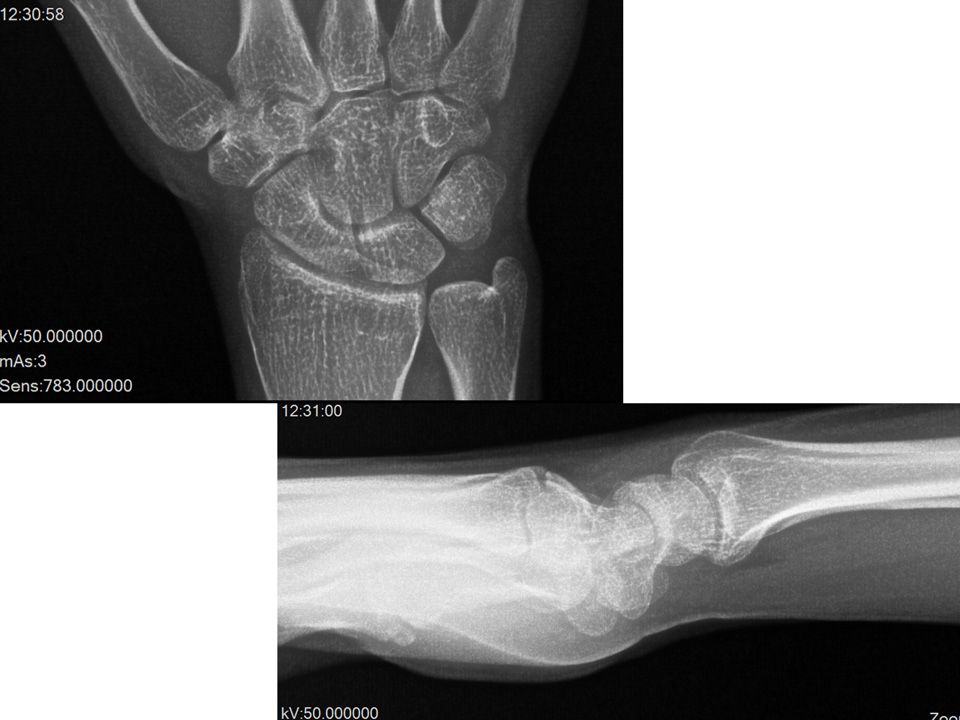

Case 09 - TFCC Injury 39 yr, male, construction worker, right hand dominancyHe has a history of right wrist distorsion 3 years agoFovea test +